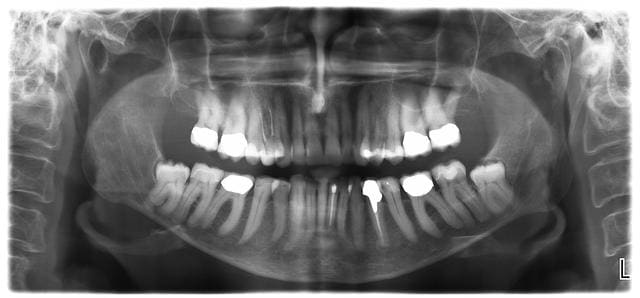

Des sagesses de toutes les formes vous attendent... Ca c etait ce matin...

Apres examen CBCT on laisse la 48 en place et si nouvel episode douloureux, coronectomie partielle.

Ps Sur la pano, 8 couronnes et une dent devitalisee(patiente de 75 ans). On a pas la meme secu.

Qui veut faire la 38?